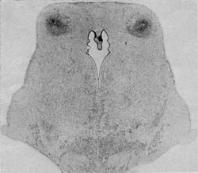

Figure 1 - Damage in the inferior colliculi of an infant monkey, caused by a brief episode of total asphyxia at birth. From Myers (1972). |